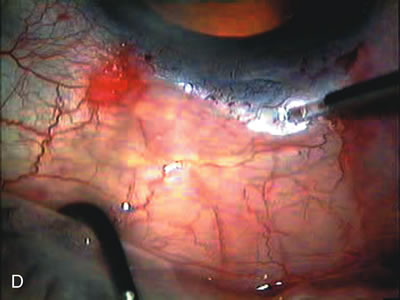

Fig. 3. Partial bleb failure following clear corneal phacoemulsification with foldable IOL. A. Preoperative bleb appearance prior to temporal lens extraction. Preoperative IOP was 12 mm Hg on no antiglaucoma medications. Time from 5-FU trabeculectomy surgery to lens extraction was one year. B. Bleb appearance 2 months after clear corneal cataract surgery with topical anesthesia. Following lens extraction, increased vascularity was noted along with decreased size of the filtering bleb. IOP increased to 20 mm Hg as early as 2 weeks after surgery, necessitating topical antiglaucoma therapy. C. High magnification view of bleb before lens extraction demonstrates diffuse pale bleb. D. High magnification view of bleb 2 months after surgery. There are vessels surrounding the nasal side of the bleb and the overall bleb size is smaller.

Fig. 1. The anatomic advantage of small incision cataract surgery for the glaucoma patient. A. Long-term bleb function with a large cataract incision is difficult to achieve with either ECCE-trabeculectomy or trabeculectomy followed later by ECCE. This bleb failed to form sufficiently when combined with large incision ECCE. The inflammation, bleeding, and long-term wound healing with stimulation of fibroblasts associated with this technique are more likely to cause bleb failure. In addition, the increased iris manipulation necessary to deliver the nucleus and subsequent iris repair adds to the long-term breakdown of the blood aqueous barrier. B and C. Two-site phacotrabeculectomy has the advantage of small incision cataract surgery combined with separate site trabeculectomy. The incision size is one third the size of the standard ECCE. The inflammation is less severe, and cataract wound healing is confined to the temporal area. Visual rehabilitation with phacoemulsification and foldable IOL is much faster. Phacoemulsification allows successful lens extraction even in the unfriendly environment of a smaller pupil compared with ECCE. The trabeculectomy is performed in an entirely different site, well away from the wound healing associated with temporal phacoemulsification. The likelihood of this filter functioning long-term is greater than with ECCE-trabeculectomy. D. The surgeon also has the option of single-site phacotrabeculectomy with foldable IOL. Both the lens extraction and trabeculectomy are performed through one small 3.5-mm limbal incision.